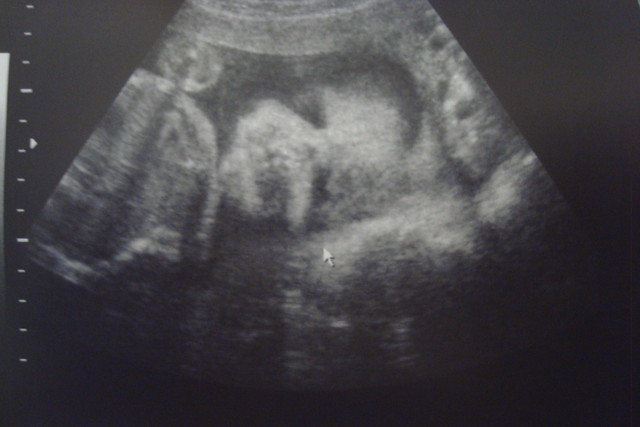

這次產檢拿到的超音波照片是"寶寶的正面照"!!!!

老實說,我自己都看不出來像爸爸還是像媽媽....

一整個比較像外星人耶...Orz